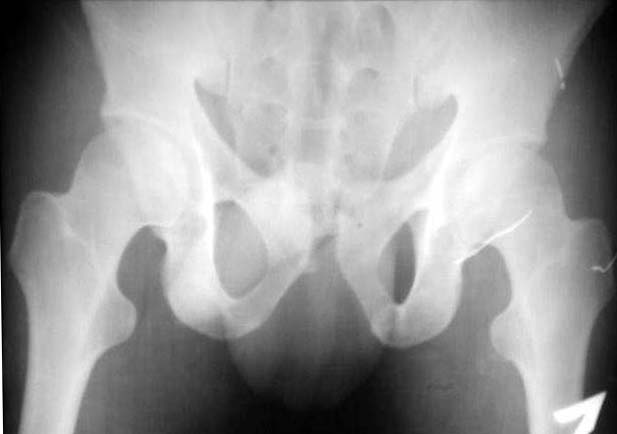

Согласно договоренности посылаю R-граммы

Во-1-х, там справа виден заголовочек "Файл-вложение", но раз трудности - переложил еще и прямо в собщение.